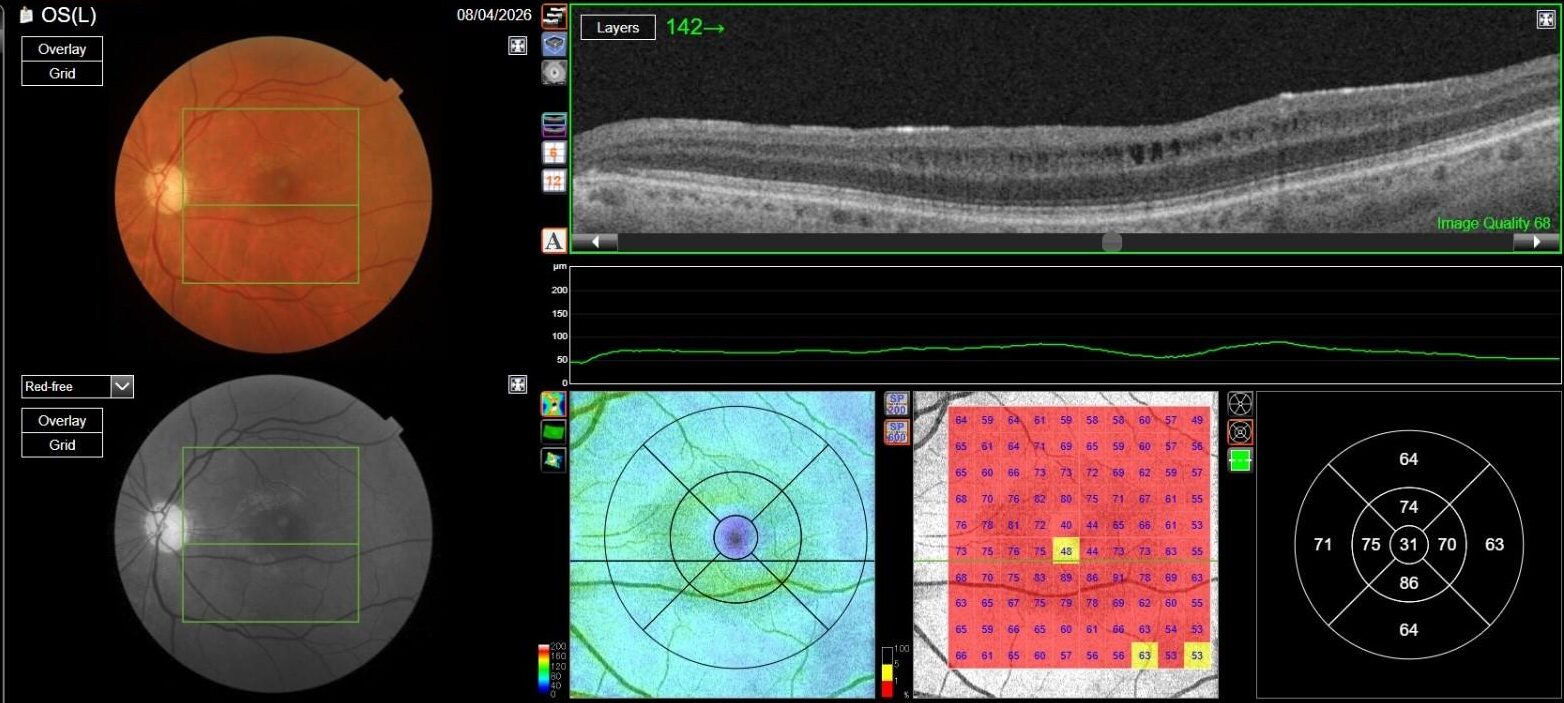

OCT in OD was normal, while in OS it showed multiple, well-defined small hyporeflective cystic spaces localized to the inner retinal layer (INL) in the perifoveal area, alongside with extreme thinning of the retinal nerve fiber layer (RNFL), whose profile and reflectivity were barely noticeable.

OCT-A was also performed in OS and, as expected, turned out to be negative. This also allowed an OCT en-face acquisition and subsequent segmentation at INL, which clearly showed the perifoveal distribution pattern of the INL cystic spaces previously found on b-scan OCT, with complete encompassing of the fovea and relative predominance in the inferior macular region.

That being said, our case allows for some interesting considerations: on one hand, MME was only found in her left eye, where the optic neuropathy was more severe, thus confirming the available literature data; on the other hand, however, en-face OCT clearly shows involvement of both inferior and superior hemiretina, although a relatively prevalent involvement of inferior hemiretina can be observed. This could either be explained by a more diffuse and severe RNFL and GC involvement, as demonstrated by both RNFL and GCC analysis, or by cohexistance of other, previously unrecognized optic neuropathy in addition to glaucomatous optic neuropathy. Lastly, no ERM was found on OCT, thus complying with evidence suggesting that vitreomacular traction may play a role in MME formation, but mainly as a concurrent cause rather than a primary pathogenetic element.